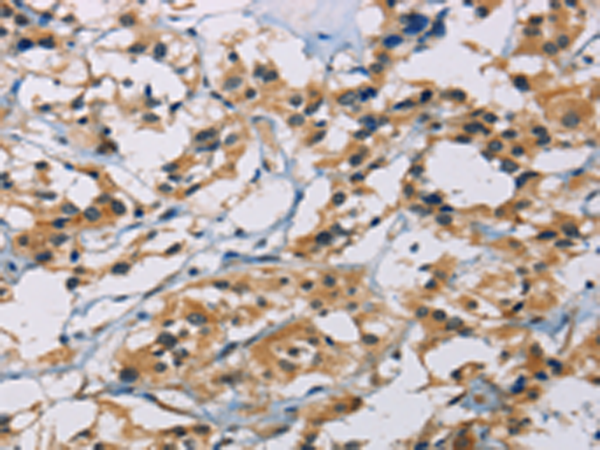

分类: 科研抗体货号: P07998别名: M6A; GPM6应用: WB,IHC反应种属: Human, Mouse, Rat